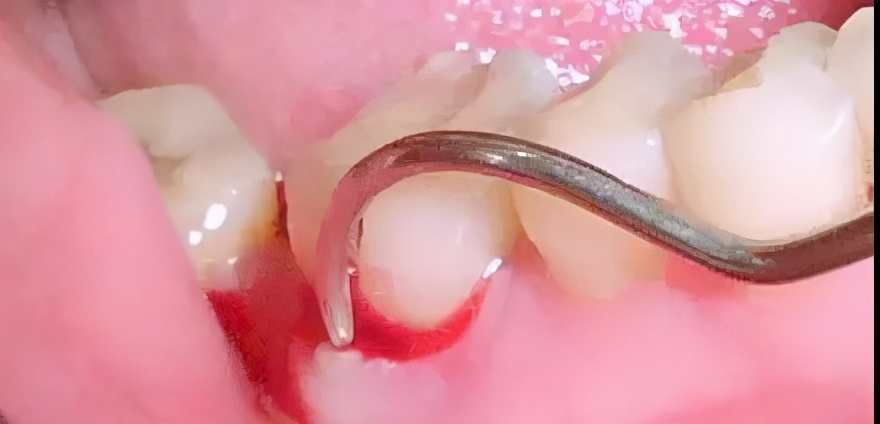

当你的牙龈出现明显的炎症,那么在洗牙时,牙龈组织受到了洁治器械的刺激便会出血。

所以,这就是为什么有些患者在洗牙过程或者洗完牙后会有出血的现象,这并非医生的操作有问题,而是牙龈有炎症所致。当然了,洗牙后出血也不用太担心,只要全身健康、血凝状态正常,出血的现象很快就会消失。